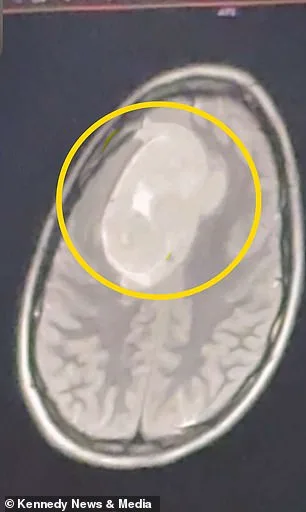

"I couldn't even move. I had to lay in the dark, and my head was shaking," Keating recounted, her voice taut with memory. The symptoms had escalated over months, yet her initial care team had shown no urgency. It wasn't until she returned home for Christmas break that a second doctor, noticing the pattern, ordered an MRI. By January 2026, the scan revealed a tumor the size of a tennis ball, pressing against the left frontal cortex — the region of the brain that governs language, motor control, and decision-making. The tumor was benign, but its location made the stakes excruciatingly clear.

A six-hour craniotomy followed, during which surgeons removed a portion of her skull to access and excise the mass. The procedure, while successful in fully removing the tumor, came with a grim reminder: if left untreated, the growth could have caused irreversible personality changes, cognitive decline, or motor dysfunction. Doctors suspected the tumor had been developing for three to four years, quietly growing until it reached a critical threshold. "I was stunned. That was the last thing I would have expected," Keating said, her words laced with disbelief.